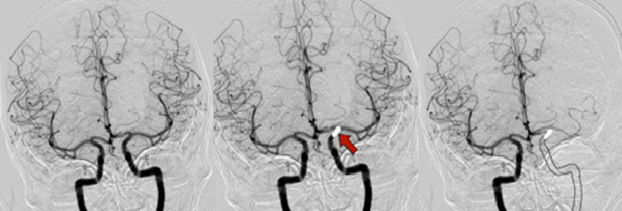

Kopš 2016. gada endovaskulāra trombektomija ir apstiprināta kā pirmās izvēles metode pacientiem ar išēmisku insultu un lielo cerebrālo artēriju oklūziju priekšējās cirkulācijas teritorijā, ja kontrindicēta intravenoza trombolīze. Šis pētījums veltīts līdz šim pietiekami neizpētītiem jautājumiem: atsevišķu ārstēšanas metožu salīdzinājumam, salīdzinot rezultātus ar kombinētas terapijas grupu (intravenoza trombolīze, kurai seko endovaskulāra trombektomija). Pētījumā vērtēti radioloģiski diagnostiskie kritēriji (piemēram, kolaterālā asinsapgāde, oklūzijas vieta, insulta plašums), kas varētu palīdzēt pacientu atlasē aktīvai ārstēšanai un sasniegt pēc iespējas labāku vēlīno klīnisko iznākumu.

Darba mērķis bija izvērtēt akūta išēmiska insulta multimodālas datortomogrāfijas diagnostikas un aktīvas ārstēšanas taktikas saistību ar radioloģisko un klīnisko iznākumu. Pētījumā tika iekļauti 288 pacienti ar akūtu išēmisku insultu pacientiem ar lielo cerebrālo asinsvadu oklūziju.

Pētījumā konstatēts, ka labam klīniskajam un radioloģiskajam iznākumam vitāli svarīga ir pacientu mērķtiecīga atlase, izmantojot tādus kritērijus kā kolaterāļu raksturojumu, potenciāli glābjamo smadzeņu audu apjomu, laiku līdz rekanalizācijai. Rezultāti arī parādīja, ka klīniskais iznākums būtiski neatšķīrās starp pacientu grupām priekšējās cirkulācijas teritorijā, salīdzinot izolētas trombektomijas vai kombinētas terapijas grupas, taču šo grupu rezultāti bija viennozīmīgi labāki nekā izolētai intravenozai trombolīzei. Savukārt pacientiem ar išēmisku insultu mugurējās cirkulācijas teritorijā kombinēta terapija uzrādīja labākus rezultātus nekā izolēta trombektomija.